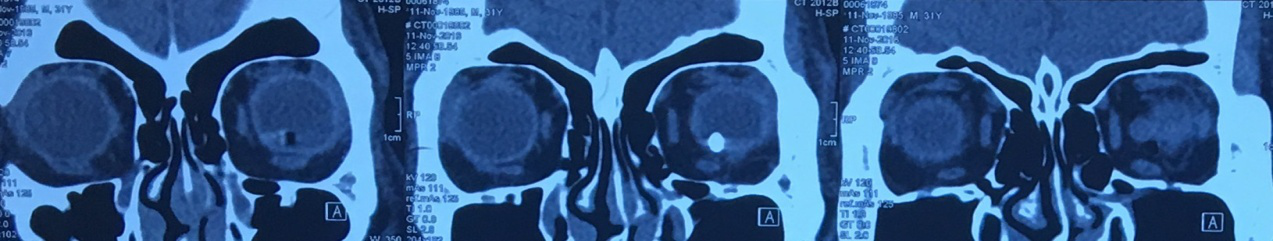

2.阅片记录

2016年11月11日眼眶CT片示:左眼球内异物影,余未见明显异常。

2016年11月11日眼眶CT片